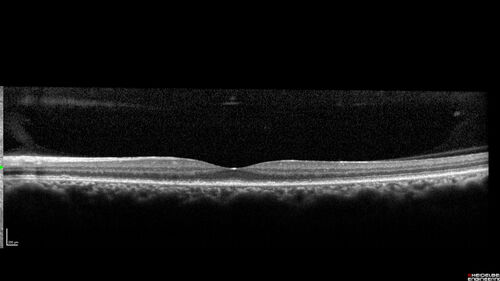

Ocular Lymphoma - Initially presented like auto-immune retinopathy

43 year old man: initial presentation - The vision in the left eye is blurry and opaque for about 2 weeks.  In the central of the vision, when he covers the right eye, in the center of the left eye there is a film with a light in the middle.  This has never happened before.  He has not been sick for the last few months.  A few weeks ago he saw waves on the floor when looking down but that has gone away.  Since the vision loss started the vision has not changed much.  The central vision is not getting better.

VA improved over 2 months to normal.  Then the patient had 2 more episodes of self-limited vision loss (no treatment).  Then 2 years later he presented with a diagnosis of CNS lymphoma and later developed subretinal deposits (last images)